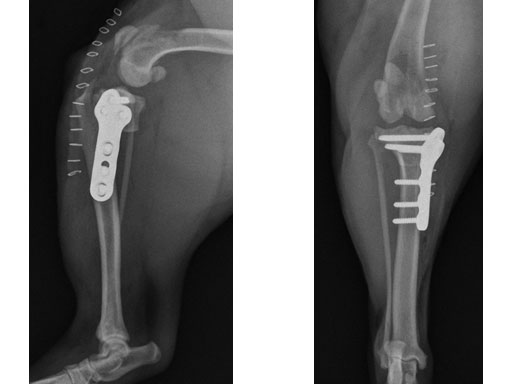

The stifle joint was surgically explored. All remaining remnants of the torn cranial cruciate ligament were debrided; in addition, the caudal pole of the medial meniscus was torn/crushed, and a partial meniscectomy of the damaged portion was performed. A TPLO plate 3.5 was applied to stabilize the fracture. The plate was applied in a neutral fashion. Postoperative x-rays revealed a tibial plateau angle of 5, and a correction of the torsion to 0 mm.

Follow-up x-rays at 8 weeks postoperatively revealed that the osteotomy had healed, and the dog was doing very well. The identical procedure was performed on the opposite stifle joint 2 months later. Healing was again obtained 8 weeks postoperative. Presently, the dog is about 1 year postoperatively and functioning very well.